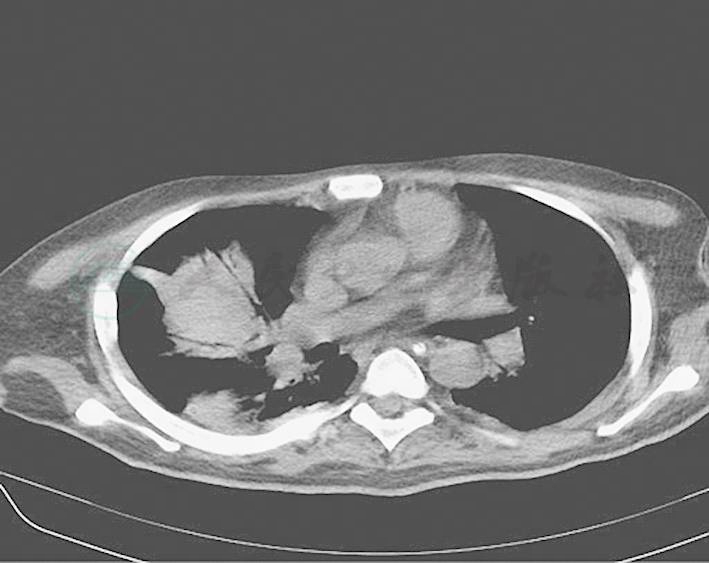

头颅、胸部及全腹部CT检查:①右侧额颞顶部术后,左侧额叶、颞叶片状低密度影,考虑软化灶;②右侧颞骨骨折;③右中下肺肺不张伴感染,两侧胸膜增厚伴少量胸腔积液,两下胸部多处肋骨皮质欠连续;④T4右侧横突骨折,右股骨干骨折,局部血肿伴边缘机化可能;⑤盆腔少量积液(图1)。

图1 ①右侧额颞顶部术后,左侧额叶、颞叶片状低密度影;②右中下肺肺不张伴感染,两侧胸膜增厚